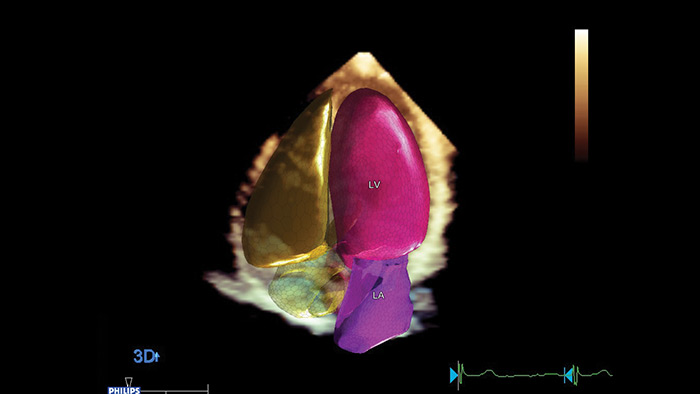

Ilościowa ocena funkcji mięśnia sercowego podnosząca pewność rozpoznań Aplikacja Philips Dynamic HeartModelA.I. Umożliwia wykonywanie wiarygodnych powtarzalnych pomiarów 3D frakcji wyrzutowej. Pomiar trwa mniej niż minutę i może być wykonywany w ramach rutynowych badań.